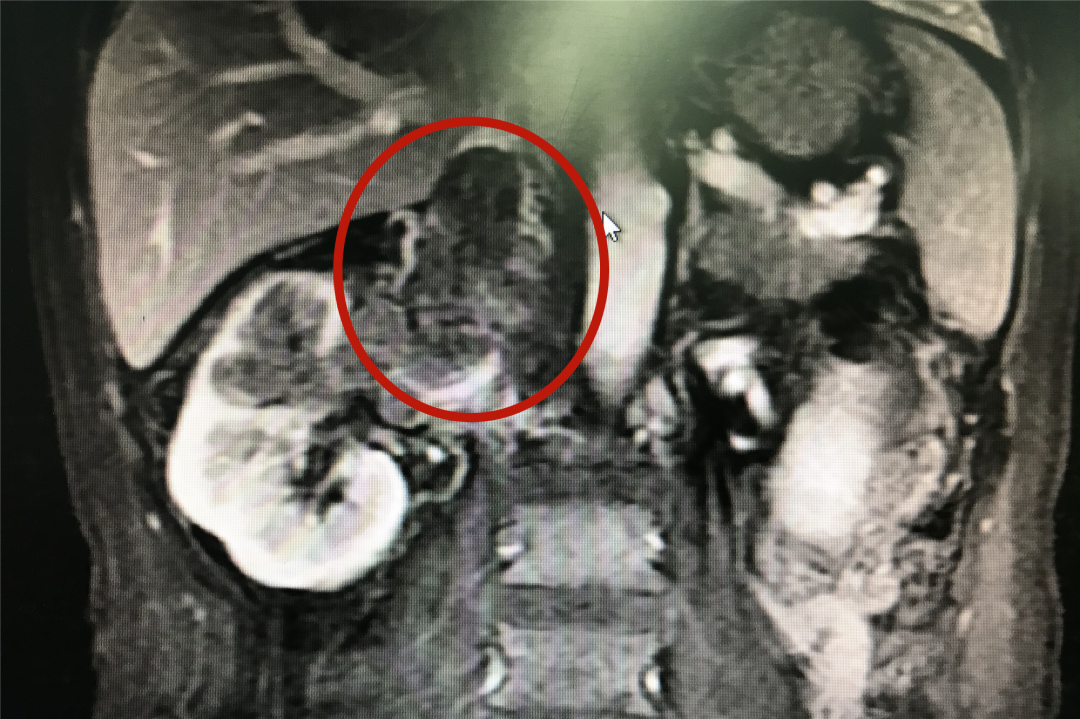

进一步的CT检查更让人捏一把汗!王大伯的肾脏肿瘤不但巨大,而且蔓延至下腔静脉,形成10余公分长的癌栓,且往心脏方向蔓延。

王大伯下腔静脉内巨大的癌栓▲